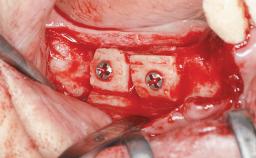

A 45-year-old woman with a completely edentulous maxilla was referred to evaluate the possibility of rehabilitation with an implant-supported prosthesis. This patient was healthy and a non-smoker. She had been wearing a maxillary complete denture opposing a natural mandibular dentition since her twenties. This situation had resulted in progressive resorption of the alveolar ridge, repeatedly creating a need for relining the denture. Twenty years later, despite multiple adaptations and the use of “glues” the denture was unstable and causing the patient psychological and functional discomfort.

Bone Augmentation Horizontal|Sinus Floor Elevation|Staged|Vertical

Augmentation Materials Autogenous chips|Autogenous block(s)

Soft Tissue Grafting Staged

Bone Volume Deficient vertically or deficient vertically AND horizontally